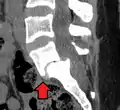

X-ray of the lateral lumbar spine with a grade III anterolisthesis at the L5-S1 level

Classification by degree of the slippage, as measured as percentage of the width of the vertebral body:[14] Grade I spondylolisthesis accounts for approximately 75% of all cases.[6]

• Grade I: 0–25%

• Grade II: 25–50%

• Grade III: 50–75%

• Grade IV: 75–100%

• Grade V: greater than 100%